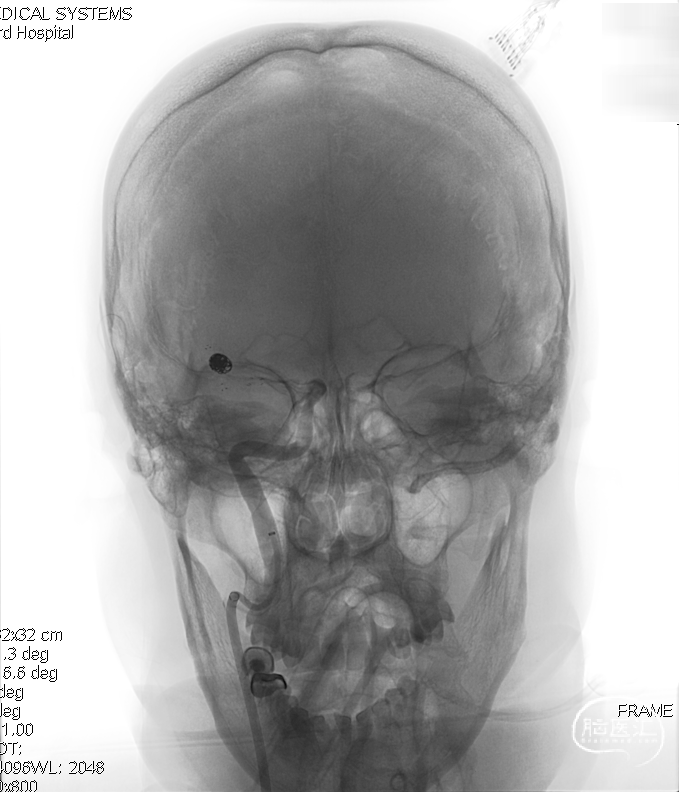

术前影像:术前工作位。

术前工作位与三维重建:显示右侧MCA分叉部未破裂动脉瘤,6.9mm*7.2mm,瘤颈7.4mm。该病例之困难在于M1迂曲成袢。